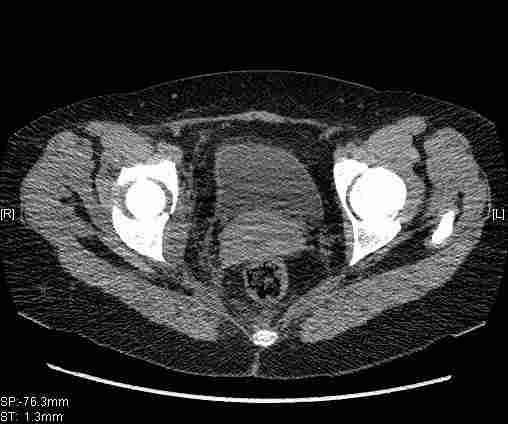

[Ortho] [1/2] Re: Т-образный перелом вертлужной впадины

Удалось сегодня вывести пациентку в соседнюю больницу, где есть кт.

Срезы сделаны  только горизонтальные.